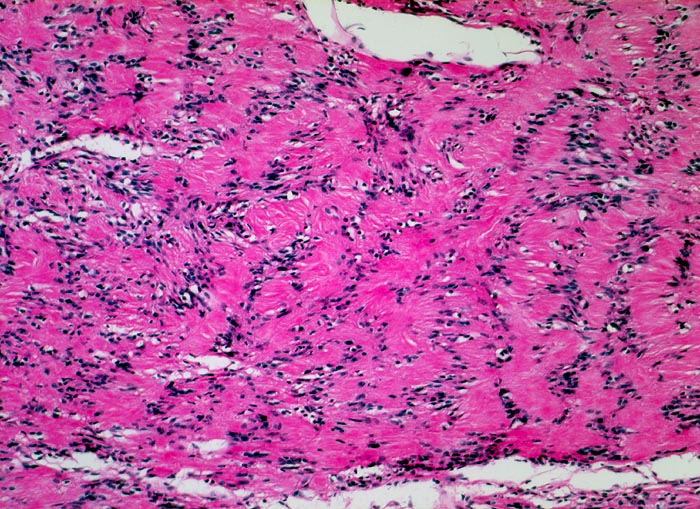

Schwannom: Verocay bodies

Palisadierung der Tumorzellkerne in parallelen Reihen. Dazwischen sind die kernlosen Zellfortsätze ebenfalls parallel angeordnet.

Immunhistochemisch sind die Tumorzellen diffus und stark positiv für S-100 Protein.

Derber abgekapselter Tumor am Nervus ulnaris

Die parallele Anordnung von Zellkernen und Zytoplasmafortsätzen nennt man Verocay body. Diese sind typisch für Schwannome können aber auch von anderen Tumoren imitiert werden (z.B. Meningeom).